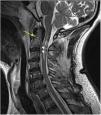

Sixty-seven-year old male without known past medical history. He suffered from syncope and cardiorespiratory arrest (CRA) while riding his bicycle and was thrown off the road. He recovered his pulse after 34min after performing basic and advanced cardiopulmonary resuscitation maneuvers. The presence of ischemic heart disease, pulmonary thromboembolism, brain hemorrhage, and ischemic disease are discarded as causes for the CRA. The cerebral magnetic resonance imaging performed showed a fracture at the base of the odontoid process (green arrow) without displacement and small anterior epidural hematoma (indicated by discontinuous white arrows) without significant mass effect (Fig. 1). All of it accompanied by a spinal cord hemorrhagic contusion (pink arrows) from the C2 up to the C3 (Fig. 2). The patient progression was poor, and he died six days after admission at the intensive care unit.